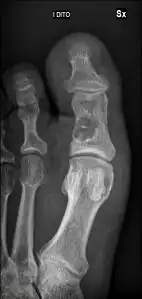

Simple bone cysts are often found incidentally on X-rays. About 90 to 95% of the lesion is found in metaphysics of long bones. The cyst is centered, oblong in shape along the long axis of a long bone. Rarely, they are large and multicameral and are found in diaphysis. When fracture is present, there may be a small bone fragment migrated in the cystic fluid. This is called "fallen fragment sign" which is diagnostic of simple bone cyst. Besides, a bubble migrating upwards (known as "rising bubble sign") is another feature suggesting of simple bone cyst.[7]

Unprovoked break in big toe, with "fallen leaf" sign. -